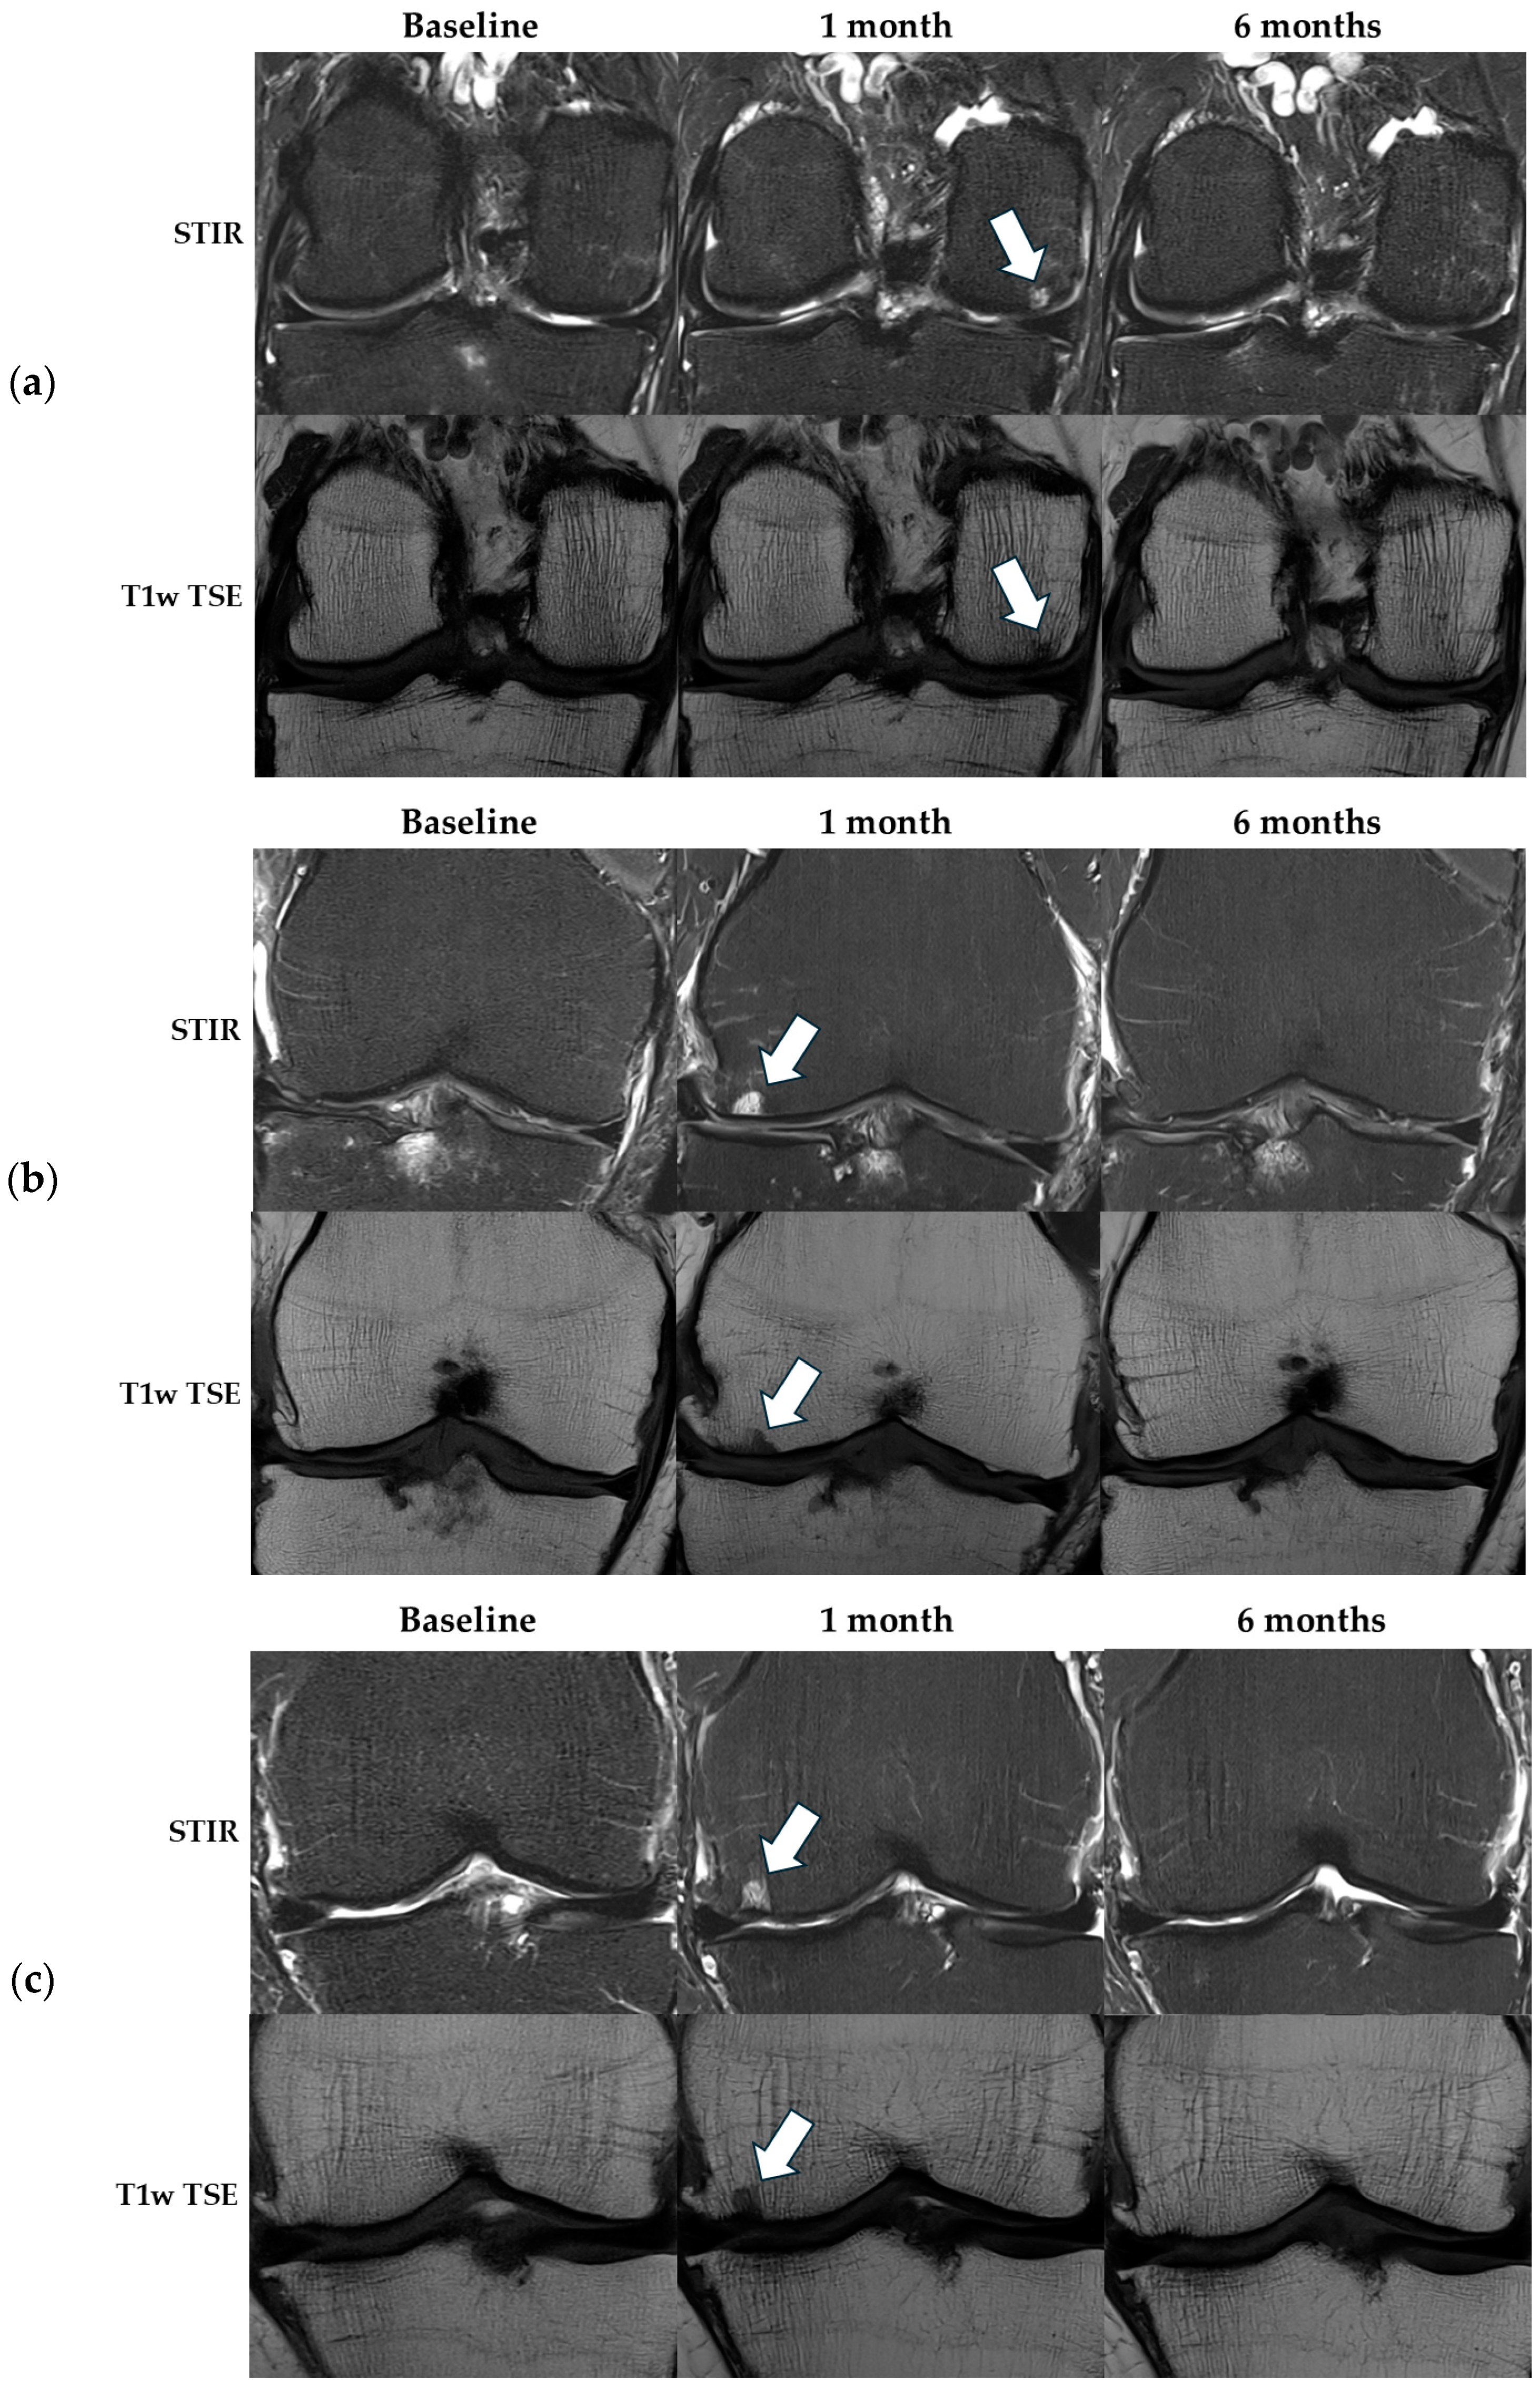

3.2.2. CE-MRI—Synovitis

| CE-MRI—Guermazi | ||||

| Whole-joint synovitis, median [IQR] | 12 [8;15] | 11 [8;14] | 11 [6;13] | X2 (2) = 6.2, p = 0.045 |

| Local synovitis, median [IQR] | 3 [2;4] | 2 [1.5;3] | 2 [1;3] | X2 (2) = 11.1, p = 0.004 |